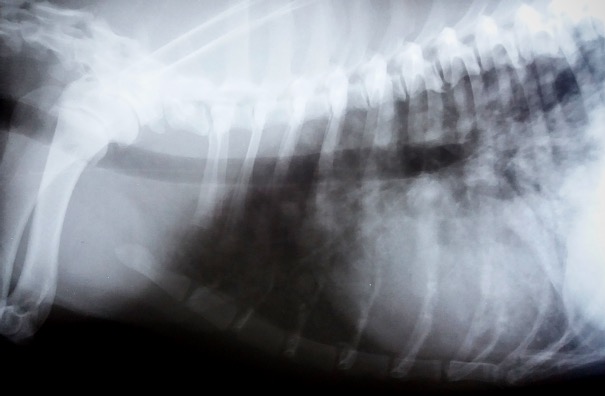

- Hasi ultrahang, mellkas röntgen, esetenként CT és MRI vizsgálat: áttétkeresés céljából.

Tüdőáttét röntgen felvétele